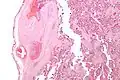

It can be diagnosed by histomorphologic examination of the placenta and is characterized by fetal vessel thrombosis and clustered fibrotic chorionic villi without blood vessels.

High mag.

High mag. -